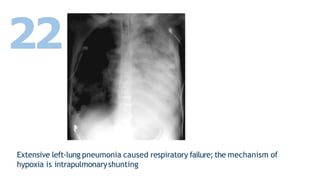

Extensive left-lung pneumonia caused respiratory failure; the mechanism of

hypoxia is intrapulmonaryshunting

22